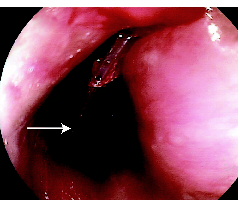

In April 2009, a 79-year-old woman was admitted to hospital with acute dysphagia. She had a history of hypertension, osteoporosis and hypercholesterolaemia. In the past she had also had a transient ischaemic attack. Her medications were felodipine, alendronate, atorvastatin and clopidogrel. Before presentation she had been eating quiche that had been heated in a plastic (polypropylene) container. At subsequent gastroscopy, a solid wedge-shaped piece of plastic 4 cm in length was found to be lodged in her upper oesophagus (Box 1). This was removed endoscopically with the aid of a stand

ard Roth Net retriever (US Endoscopy, Mentor, Ohio, USA) (a snare with a mesh basket) leaving a longitudinal mucosal tear (Box 2). There was no evidence of oesophageal perforation and she made a rapid and complete recovery, being discharged after 48 hours on pantoprazole in addition to her usual medications. At follow up after 2 weeks, she remained well and pantoprazole was ceased.